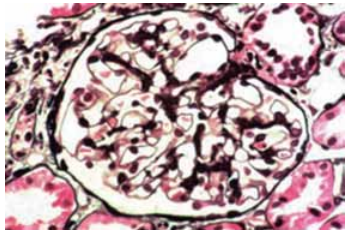

Homem de 18 anos tem diagnóstico clínico laboratorial de síndrome nefrótica há 6 meses, com complemento sérico dentro dos valores da normalidade e excelente resposta a corticoide. Foi realizada biopsia renal, que mostrou 22 glomérulos, todos com a imagem semelhante ao apresentado na figura a seguir. A imunofluorescência foi negativa.

(Coloração de prata de Jones. Disponível em: https://www.ajkd.org)

Qual é o diagnóstico da glomerulopatia?